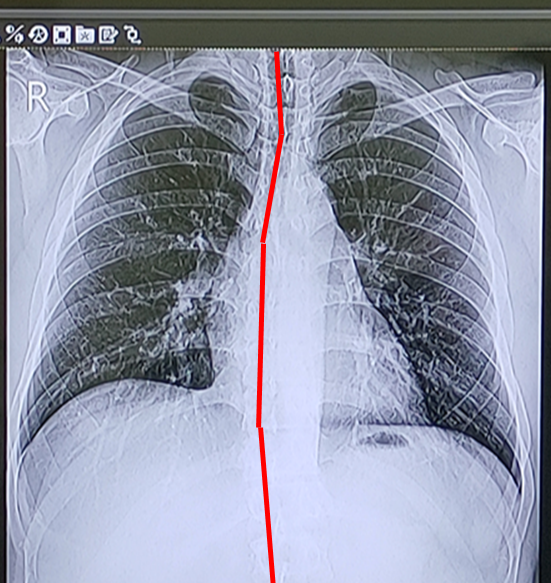

자료가 남아 있는 코로나 때문에 찍었던 X-ray 사진의 척추 중심선을 그어보면 그 심각성을 알 수 있다.

휘지 말아야할 방향으로 휘어 있는 자신의 척추를 보고 있자니...

저 휨 때문에 내 키가 얼마나 줄어들었을까와 같은 생각도 들긴하지만,